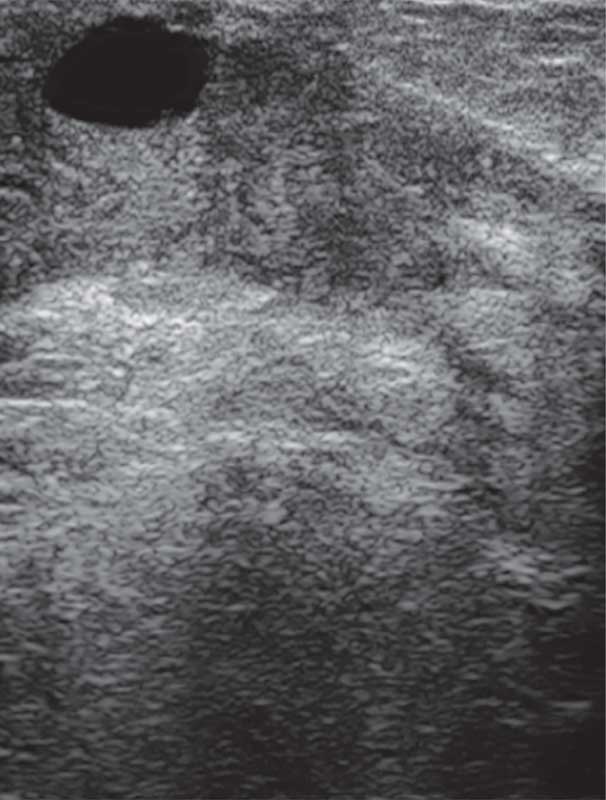

Рис. 4. Ювенильная фиброаденома левой молочной железы у 16-летней девочки

На УЗ-картине солидное, гипоэхогенное по сравнению с тканью МЖ образование однородной структуры, с четкими контурами. Нередко наблюдается дорсальное псевдоусиление без акустической тени (рис. 3–5) [5, 7, 10].